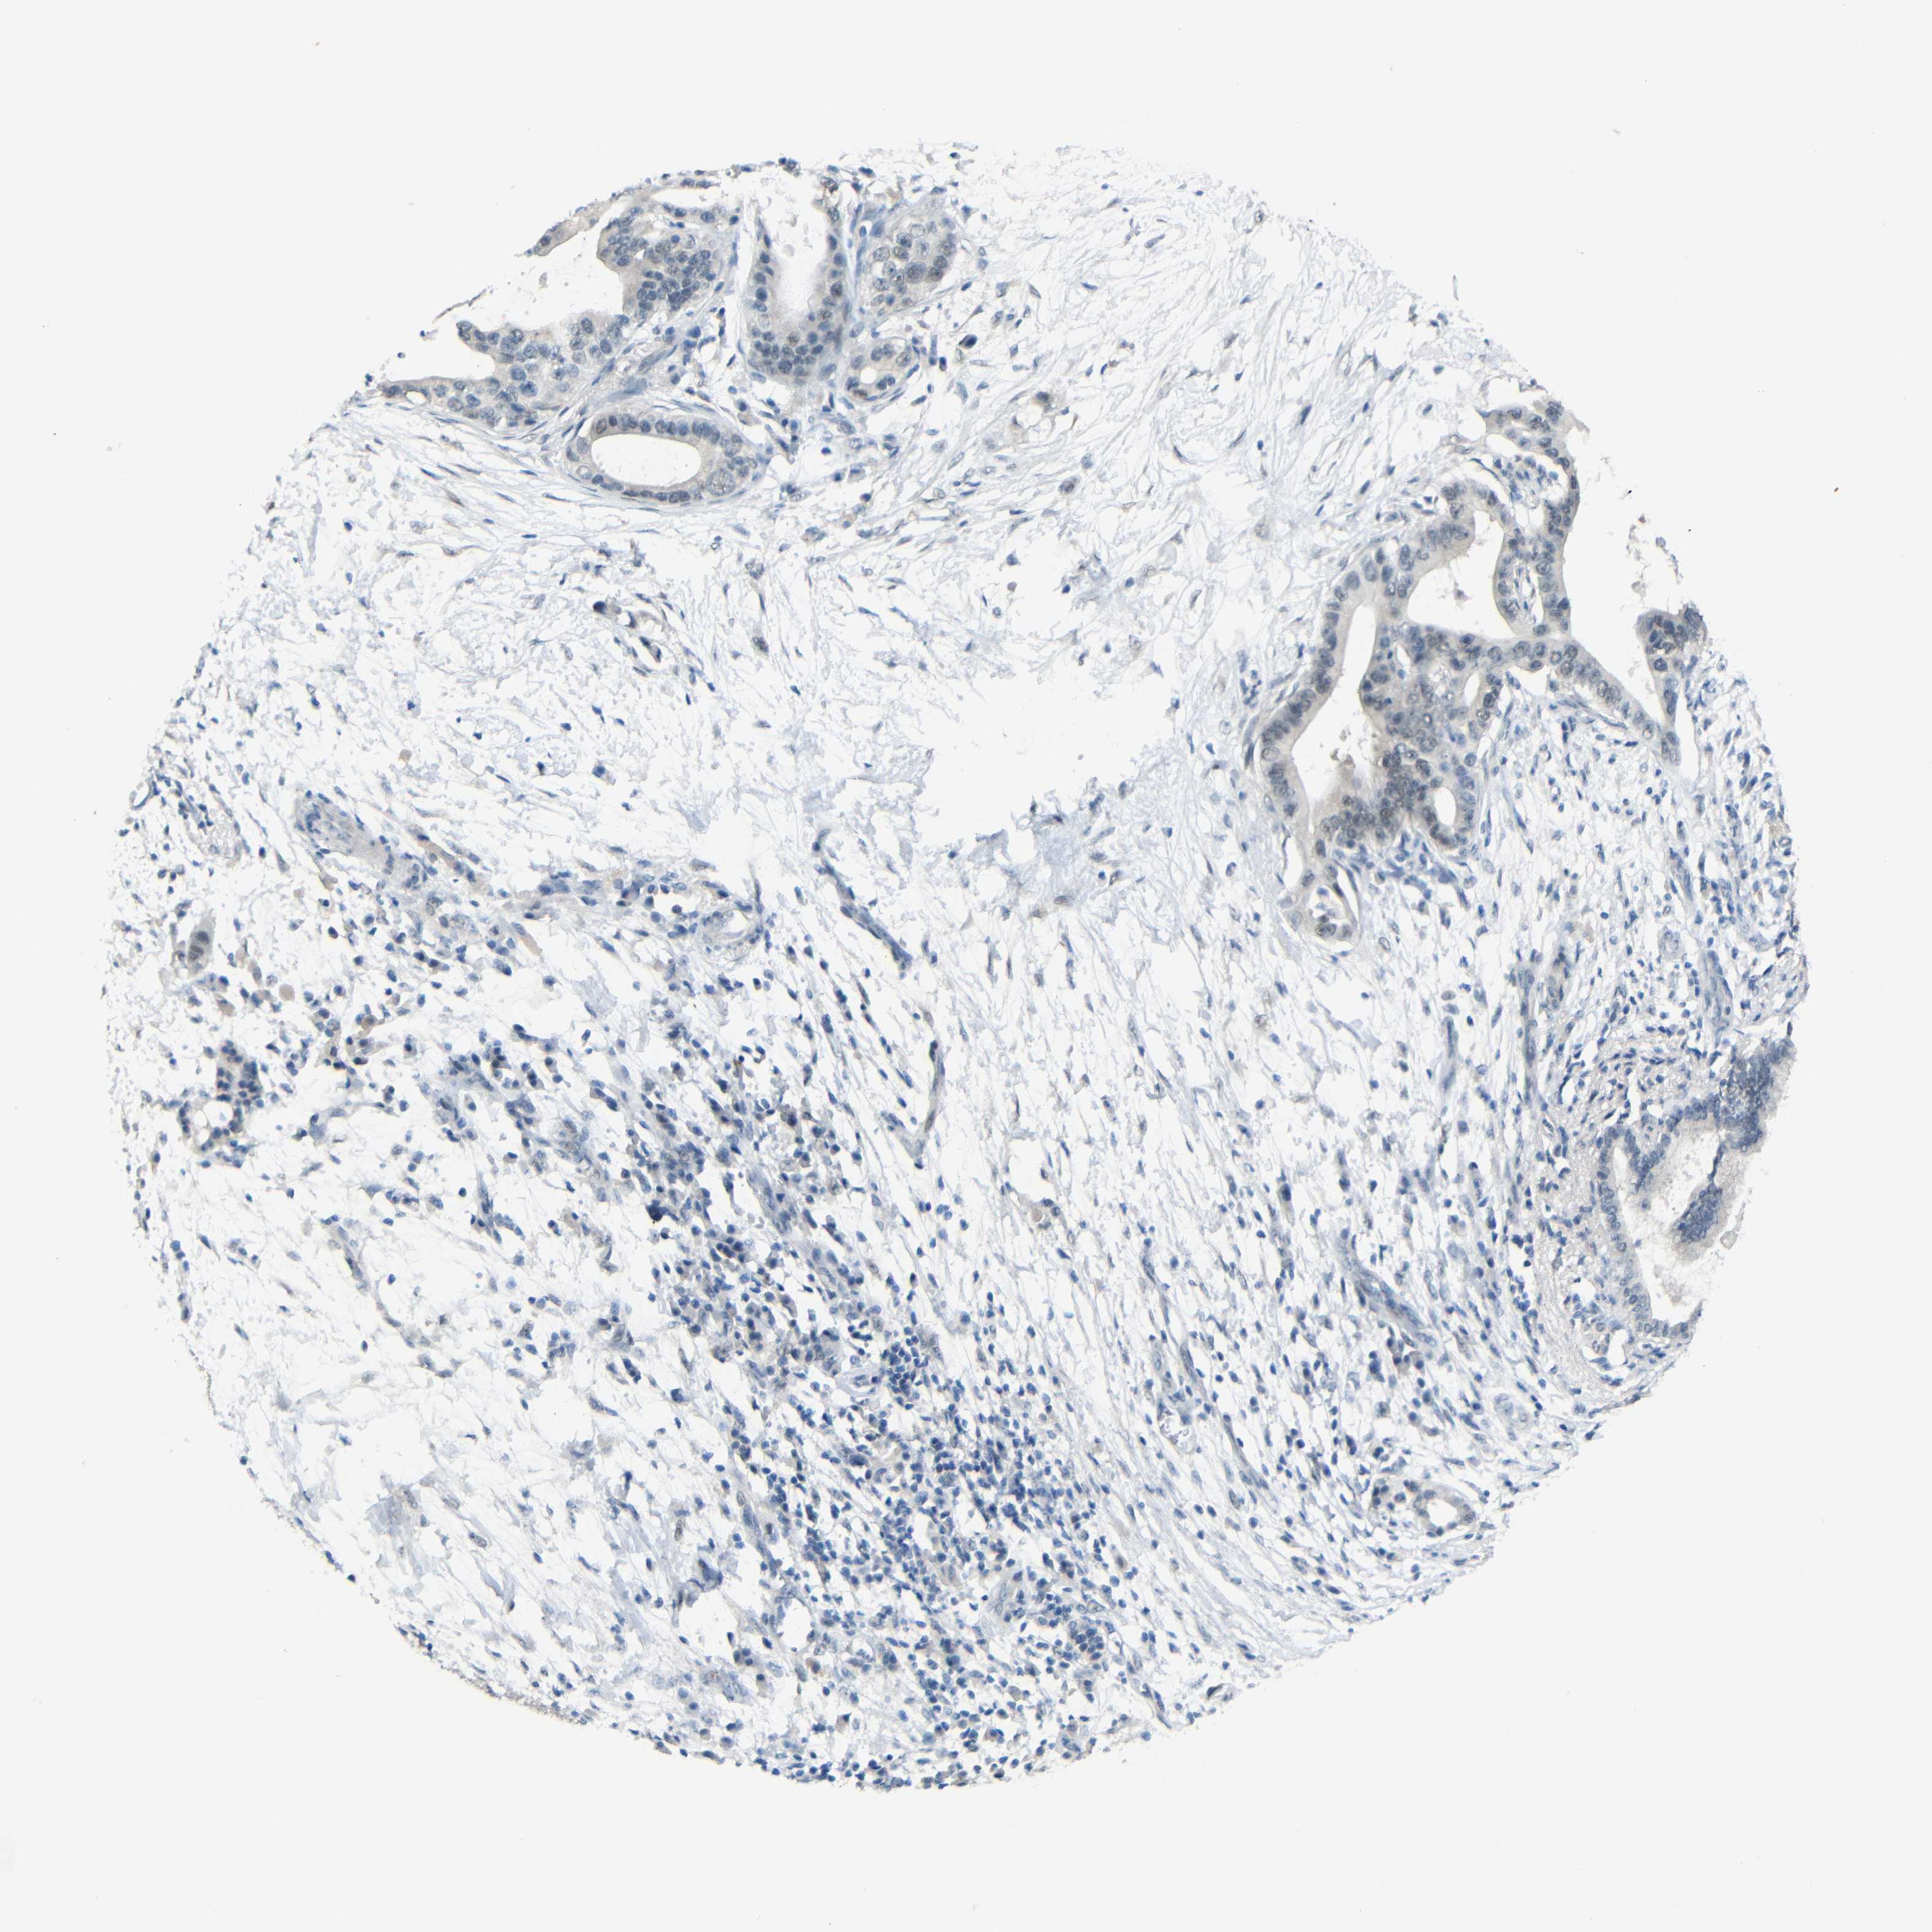

PANCREATIC CANCER - Protein expressioni

A mouse-over function shows sample information and annotation data. Click on an image to view it in a full screen mode. Samples can be filtered based on level of antibody staining by selecting one or several of the following categories: high, medium, low and not detected. The assay and annotation is described here.

Note that samples used for immunohistochemistry by the Human Protein Atlas do not correspond to samples in the TCGA dataset.

Antibody stainingi

Antibody staining in the annotated cell types in the current human tissue is reported as not detected, low, medium, or high, based on conventional immunohistochemistry profiling in selected tissues. This score is based on the combination of the staining intensity and fraction of stained cells.

Each image is clickable and will lead to virtual microscopy that enables deeper exploration of all samples and also displays staining intensity scores, fraction scores and subcellular localization as well as patient and tissue information for each sample.

Antibody HPA013185

Staining

High

Medium

Low

Not detected

Intensity

Strong

Moderate

Weak

Negative

Quantity

>75%

75%-25%

<25%

None

Location

Nuclear

Cytoplasmic/membranous

Cytoplasmic/membranous,nuclear

Adenocarcinoma, NOS